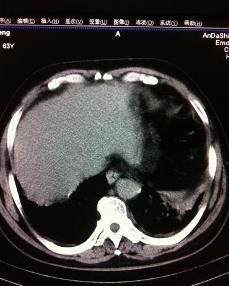

膈肌膨出症也被稱為膈膨升,屬膈肌無力類疾病,膈肌無力指膈肌活動強度的減弱,包括膈肌麻痹和膈肌膨出症。

狹義的膈肌膨出症是指:由於胚胎橫中隔內肌肉組織發育異常,導致膈肌先天性缺陷引起的膈肌膨出,稱為先天性(或原發性)膈肌膨出症。

廣義的概念通常被用來指膈肌纖維因發育不良、萎縮而異常的抬高,包括膈神經的不明病因、不明部位的損傷造成的膈肌抬高,稱為獲得性(或繼發性)膈肌膨出症。